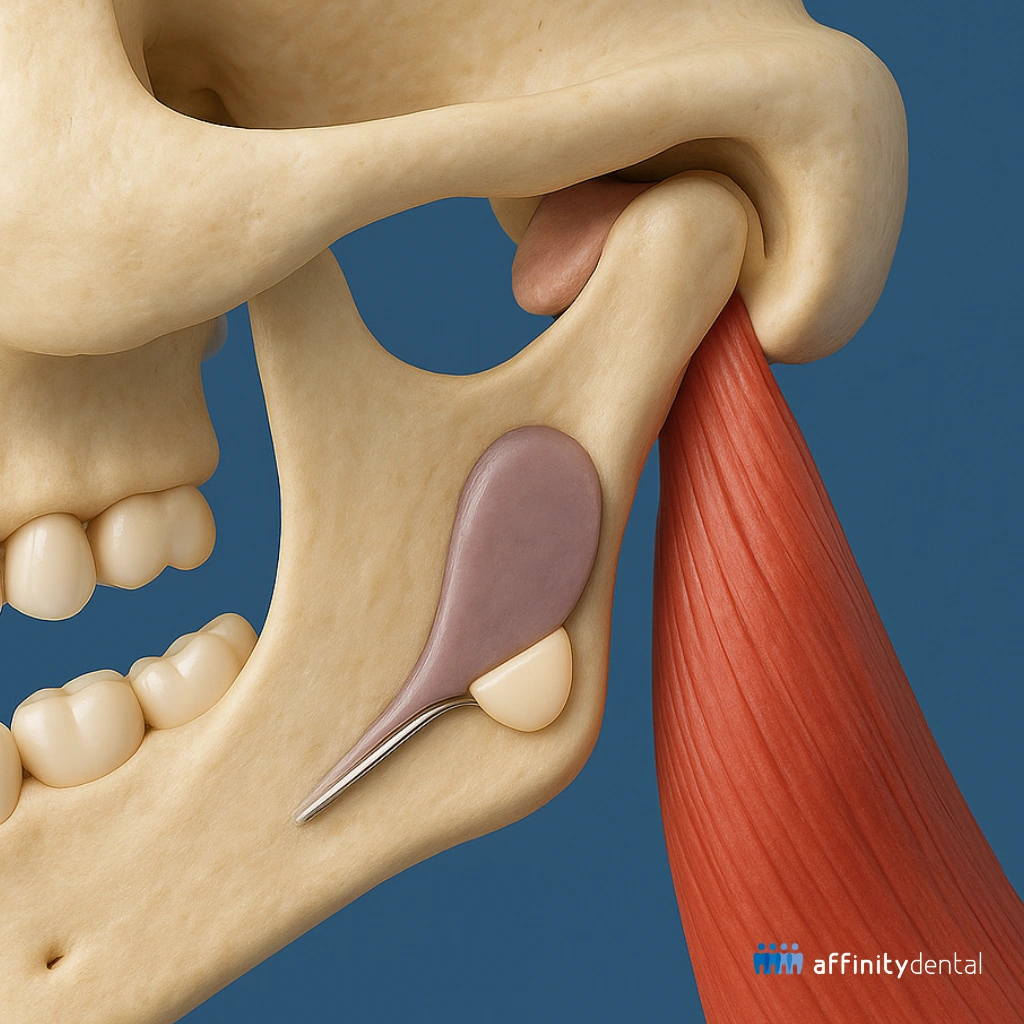

A Transcranial X-Ray is a type of lateral skull X-ray that focuses on the temporomandibular joint—the hinge that connects your jawbone to your skull, located just in front of your ears. This imaging allows your dentist or oral surgeon to see both the right and left TMJs clearly, in a closed-mouth and open-mouth position.

It captures the position, shape, and alignment of the jaw joints and the surrounding bone structures, helping us evaluate whether something is wrong—and if so, how to address it.

Because this X-ray gives a view of the joint space, bony contours, and condyle position, it is an important tool in determining whether your TMJ is healthy or if there are signs of degeneration, displacement, or inflammation.

These images give our clinicians a clear window into the condition of your TMJ—whether it’s healthy, inflamed, displaced, or showing early signs of arthritis or wear. That way, we can offer appropriate treatment, which may include: